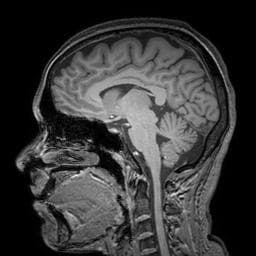

Image registration, also known as image fusion or image matching, is the process of aligning two or more images based on image appearances. Medical Image Registration seeks to find an optimal spatial transformation that best aligns the underlying anatomical structures. Medical Image Registration is used in many clinical applications such as image guidance, motion tracking, segmentation, dose accumulation, image reconstruction and so on. Medical Image Registration is a broad topic which can be grouped from various perspectives. From input image point of view, registration methods can be divided into unimodal, multimodal, interpatient, intra-patient (e.g. same- or different-day) registration. From deformation model point of view, registration methods can be divided in to rigid, affine and deformable methods. From region of interest (ROI) perspective, registration methods can be grouped according to anatomical sites such as brain, lung registration and so on. From image pair dimension perspective, registration methods can be divided into 3D to 3D, 3D to 2D and 2D to 2D/3D. Source: Deep Learning in Medical Image Registration: A Review

(Image credit: Papersgraph)